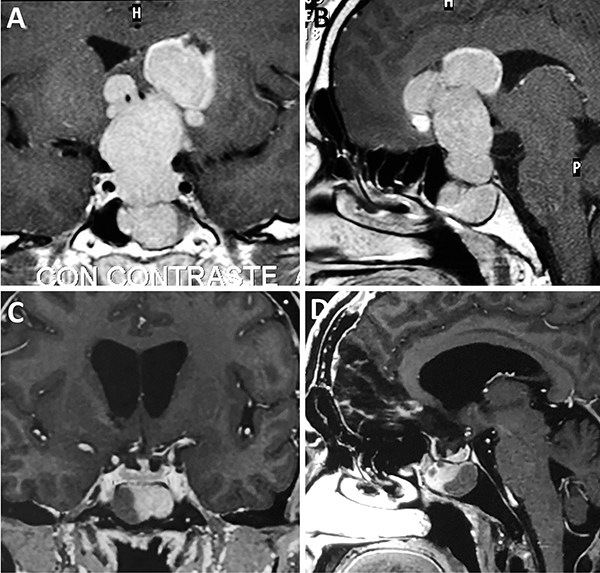

Una clasificación clásica de los adenomas es según su tamaño. Se los clasifica en microadenoma <10 mm (fig. 2), macroadenoma >10 mm (fig. 3), y adenoma gigante > 30 mm (fig. 4). Esta clasificación es importante ya que los índices de remisión están ligados al tamaño del adenoma y también su recidiva.12

Figura 4: Adenoma gigante. A-B: RM preoperatoria; C-D: RM postoperatoria.